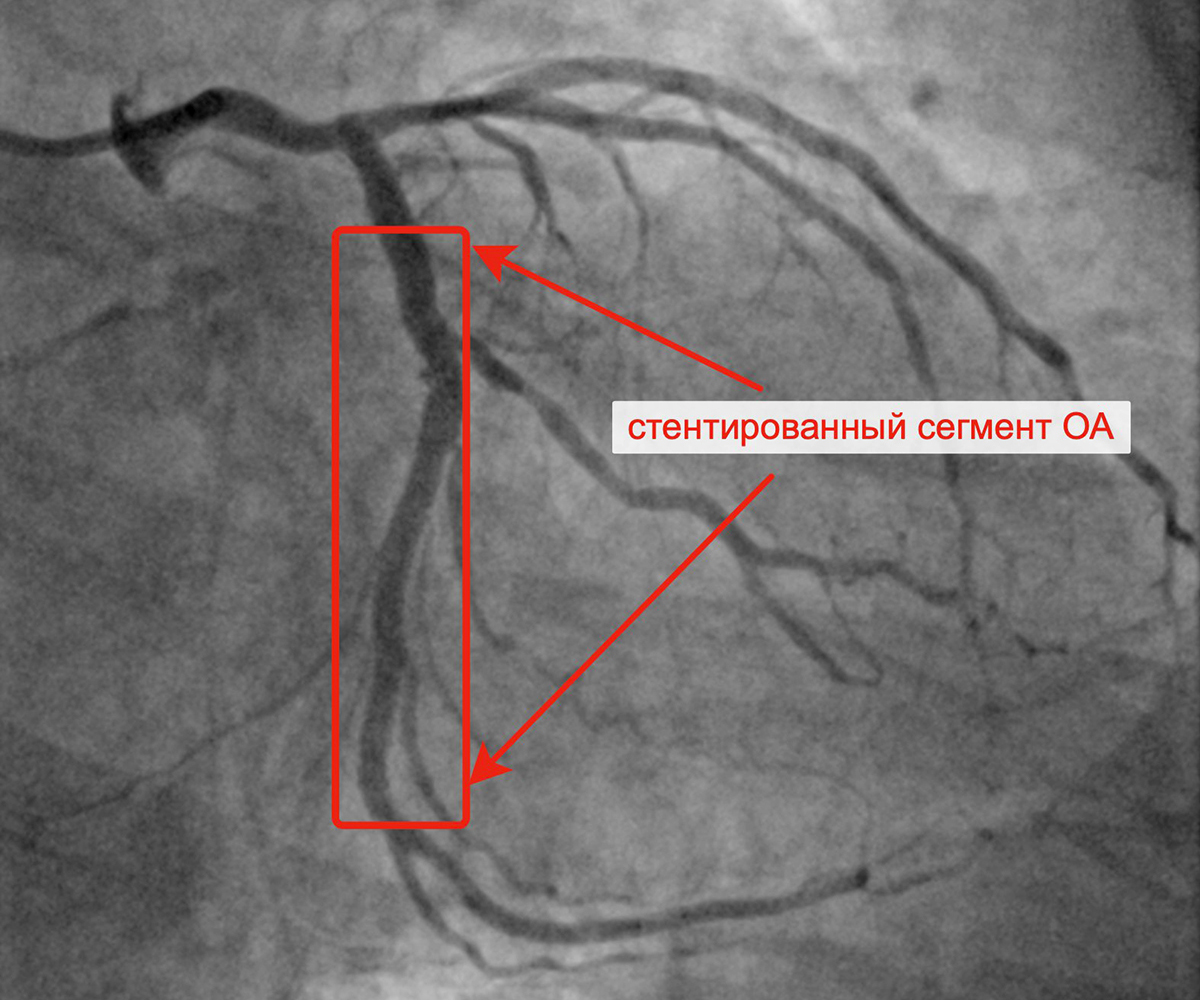

В марте 2023 г. в связи сохраняющейся одышкой, загрудинными болями при физической нагрузке пациент госпитализирован в кардиологическое отделение для решения вопроса о проведении следующего, третьего этапа реваскуляризации. Учитывая наличие ангинозных болей, результаты проведенных обследований (положительным стрессЭХО), коронарографии, наличие гемодинамически значимых стенозов коронарных артерий, принято решение о проведении баллонной ангиопластики и стентирования огибающей артерии (2 стента с лекарственным покрытием). Контрольная ангиография после успешного чрескожного коронарного вмешательства: стенты и ОА с ветвями проходимы, позиционирование стентов адекватное, диссекции или остаточного стеноза в стентированном сегменте ОА нет, кровоток TIMI 3 по ОА и всем ветвям.

Критические стенозы ОА Заведены проводники в ОА и ВТК

Имплантация первого стента в ОА Имплантация второго стента в ОА

Финальный результат имплантации 2 стентов в ОА